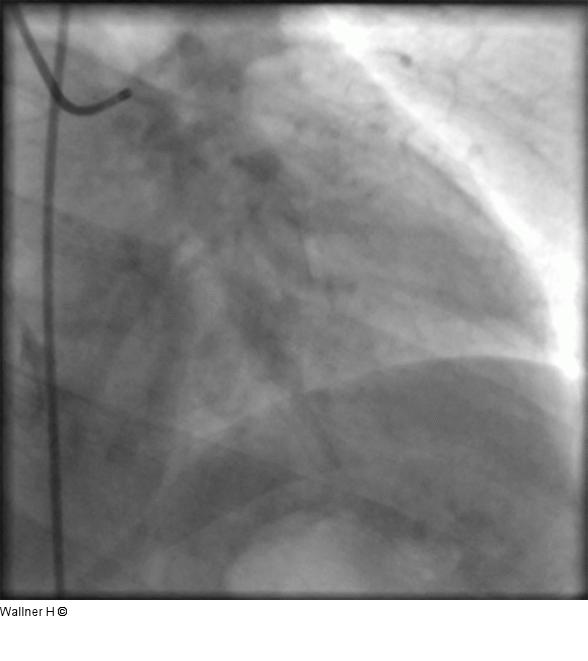

Abbildung 1: Koronarangiographie Linkes Kranzgefäß (LAO 30°/20°). Unauffälliger Hauptstamm und LAD mit Diagonalästen, proximaler Verschluß der Arteria circumflexa. |

Linkes Kranzgefäß (LAO 30°/20°). Unauffälliger Hauptstamm und LAD mit Diagonalästen, proximaler Verschluß der Arteria circumflexa. |